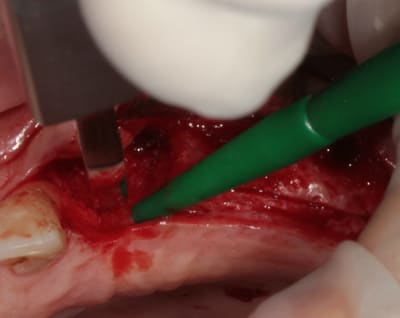

;Les photos:

1:

état initial,

disque diamanté

scie circulaire

2:

Ostéotome "lame" angulé

lame 15 (fréquent dans ce cas )

Ostéotome droit

tous sont manipulés avec douceur, mais aussi impactés avec le maillet chirurgical